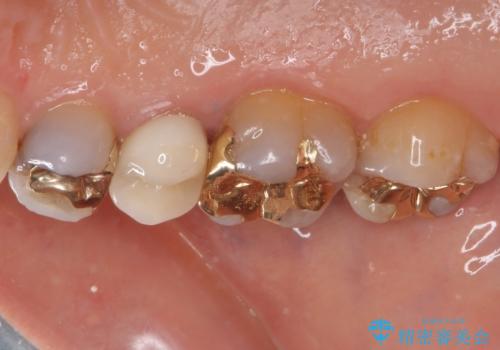

- 歯肉が退縮したためにクラウンの縁や歯根が見えてしまっていることを気にして来院された患者様です。

また、歯肉が黒く変色していることも気になるとのことでした。

仮歯に変える際に歯肉の一部を切除し、金属片による変色を除去した後、オールセラミッククラウンにて補綴することとしました。

メタルタトゥー(金属イオンの溶出による歯肉の変色)は、歯に装着された金属から金属イオンが溶け出したり、金属を除去するときの切削片が歯肉に入り込んでしまったりして引き起こされます。

物理的に除去をすることできれいな歯肉となりますが、残留している金属イオンにより再発するリスクがあります。